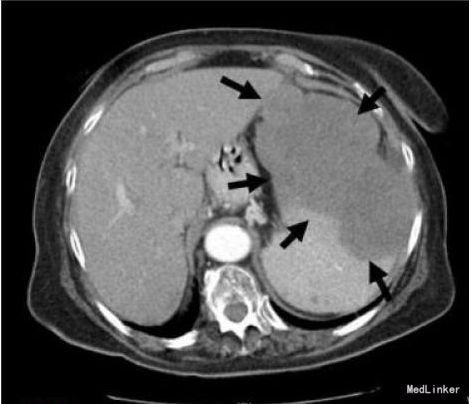

查体及辅查 腹部检查可触及脾脏显著增大。未触及外周淋巴结肿大。胸部和纵膈CT扫描除了一些与她的年龄相符的纤维化变化以外未见明显异常。未见纵膈淋巴结肿大。腹部CT扫描发现脾大,有一个明确的肿块,占据约2/3脾脏。